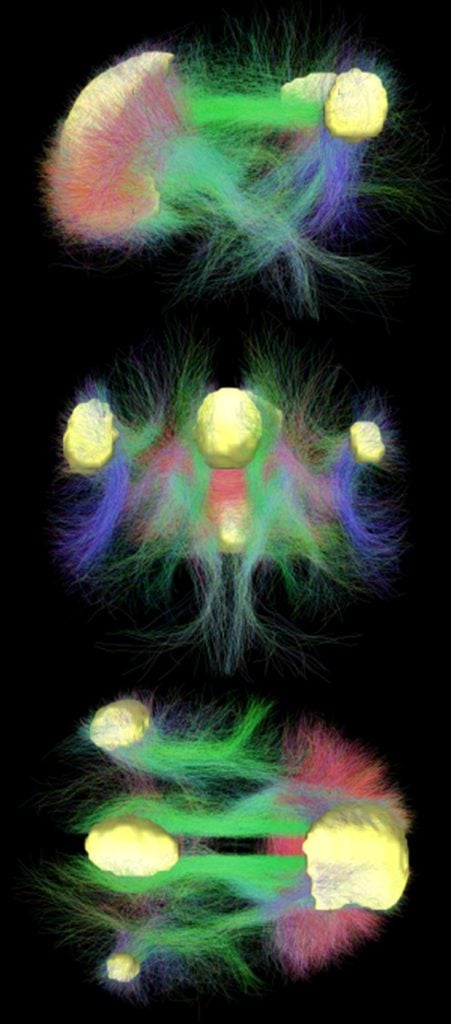

There are approximately 86 billion neurons in the human brain. That’s a lot of neurons. For reference, there are approximately 200-400 billon stars in our galaxy. Neurons are highly interconnected – our brain stimulation optimization theory is to pick the most important regions that show the highest interconnectivity. Hence, our research team chose the default mode network (DMN) as the primary target for the Vielight Neuro. Here’s why.

The Vielight Neuro targets the Default Mode Network.

- Why the Default Mode Network?

The general health of the brain is often associated with the health of the default mode network (DMN), often considered the template network of the brain. It is a large-scale brain network primarily composed of the lateral parietal cortex, posterior cingulate cortex, medial prefrontal cortex, precuneus and the entorhinal cortex. The DMN is prominent when the brain is in its quiet state of repose.[1] Several brain diseases, including Alzheimer’s Disease and Parkinson’s Disease has been associated with dysfunctional DMN.[2]

In a nutshell, the Default Mode Network (DMN) has been linked to the general health of the brain and is involved in various domains of cognitive and social processing. Do you know of a better target for brain photobiomodulation? If so, let us know.